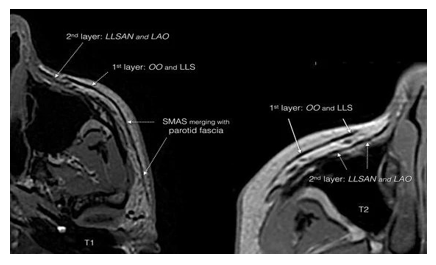

According to Herlin et al., retinacula cutis are best described as constant, dense connective structures not dependent on fat lobule architecture (Figure 1).4

Figure 1 Three-dimensional organization of the retinacula cutis distribution and density, with increased presence in the facial and palmar regions and lower density in gluteal and abdominal areas. Reproduced from Herlin et al.4